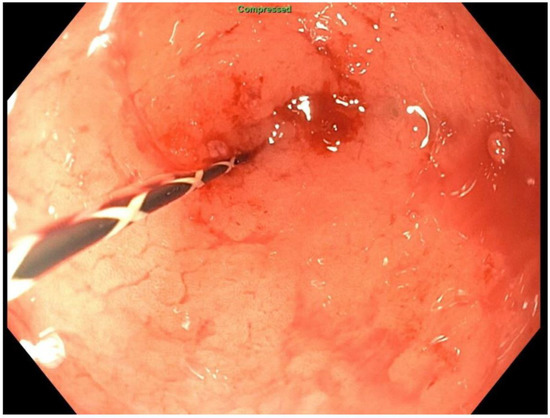

2. Detailed Case Description